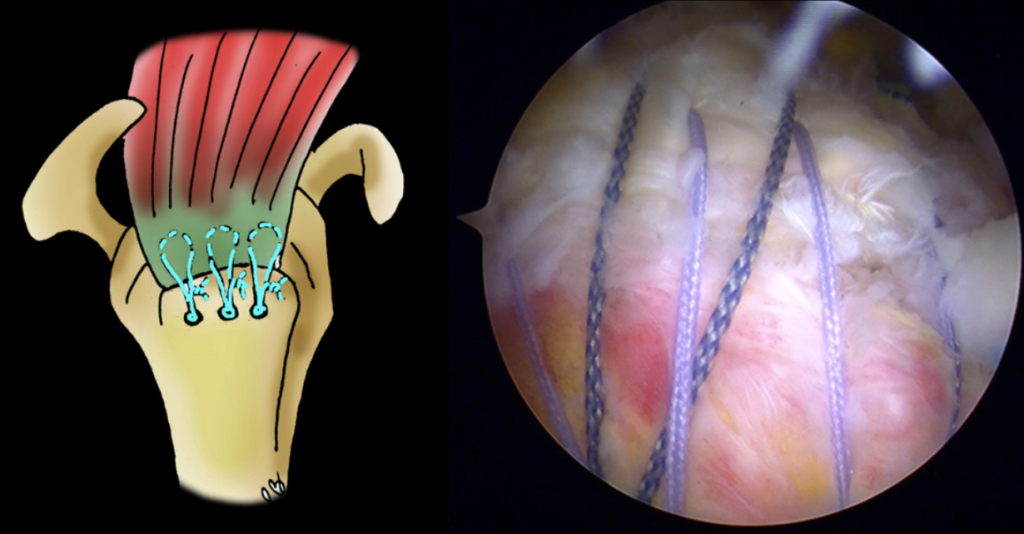

– Une réparation du ou des tendons rompus à l’aide de haubans en fil (pas de matériel métallique dans l’épaule).

Réparation du tendon par haubanage

Les résultats varient en fonction de plusieurs facteurs, mais la majorité des patients retrouvent une mobilité améliorée et un soulagement de la douleur.

Après l’intervention, le patient est immobilisé dans une attelle pendant quelques jours (entre 15 et 21 jours en général) et débute rapidement une auto rééducation (voir la section vidéo) puis une rééducation avec un kinésithérapeute. Il faut compter entre 3 et 6 mois pour une bonne récupération. Chaque patient est unique et le Dr Gastaud discutera avec vous du protocole qui s’adaptera à votre pathologie et votre opération.